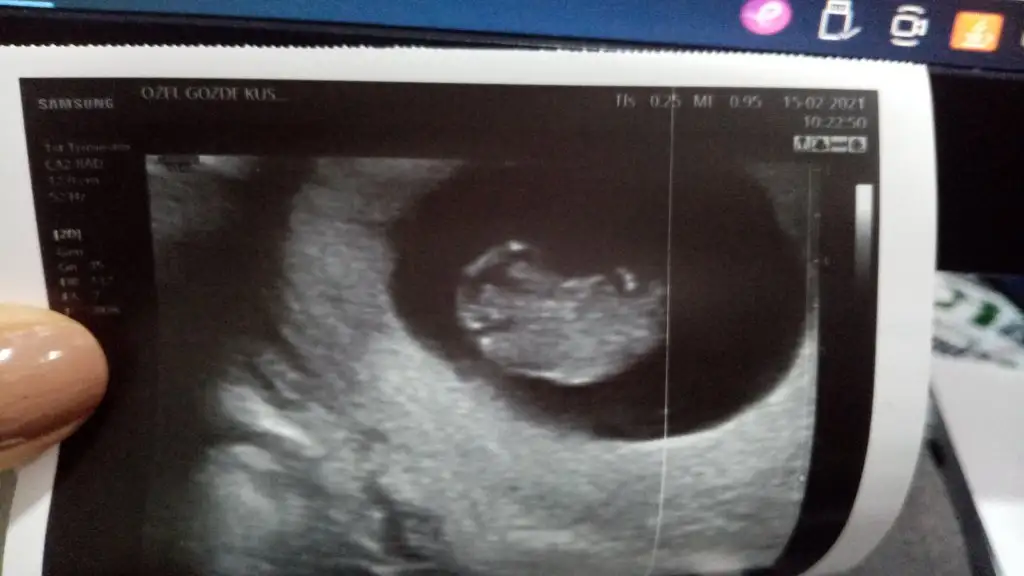

Benim ultrason görüntülerim bunun tam ters konumlusuydu, bana bir topikteki arkadaş erkek demişti ve doktorum da geçen gittiğimde erkek dedi. Hayırlısı olsun daha çok erken bizimki önceden öğrenme telaşı 🥰💃🏻

• IMG-20210215-WA0012.webp

IMG-20210215-WA0012.webp

20,8 KB · Görüntüleme: 58